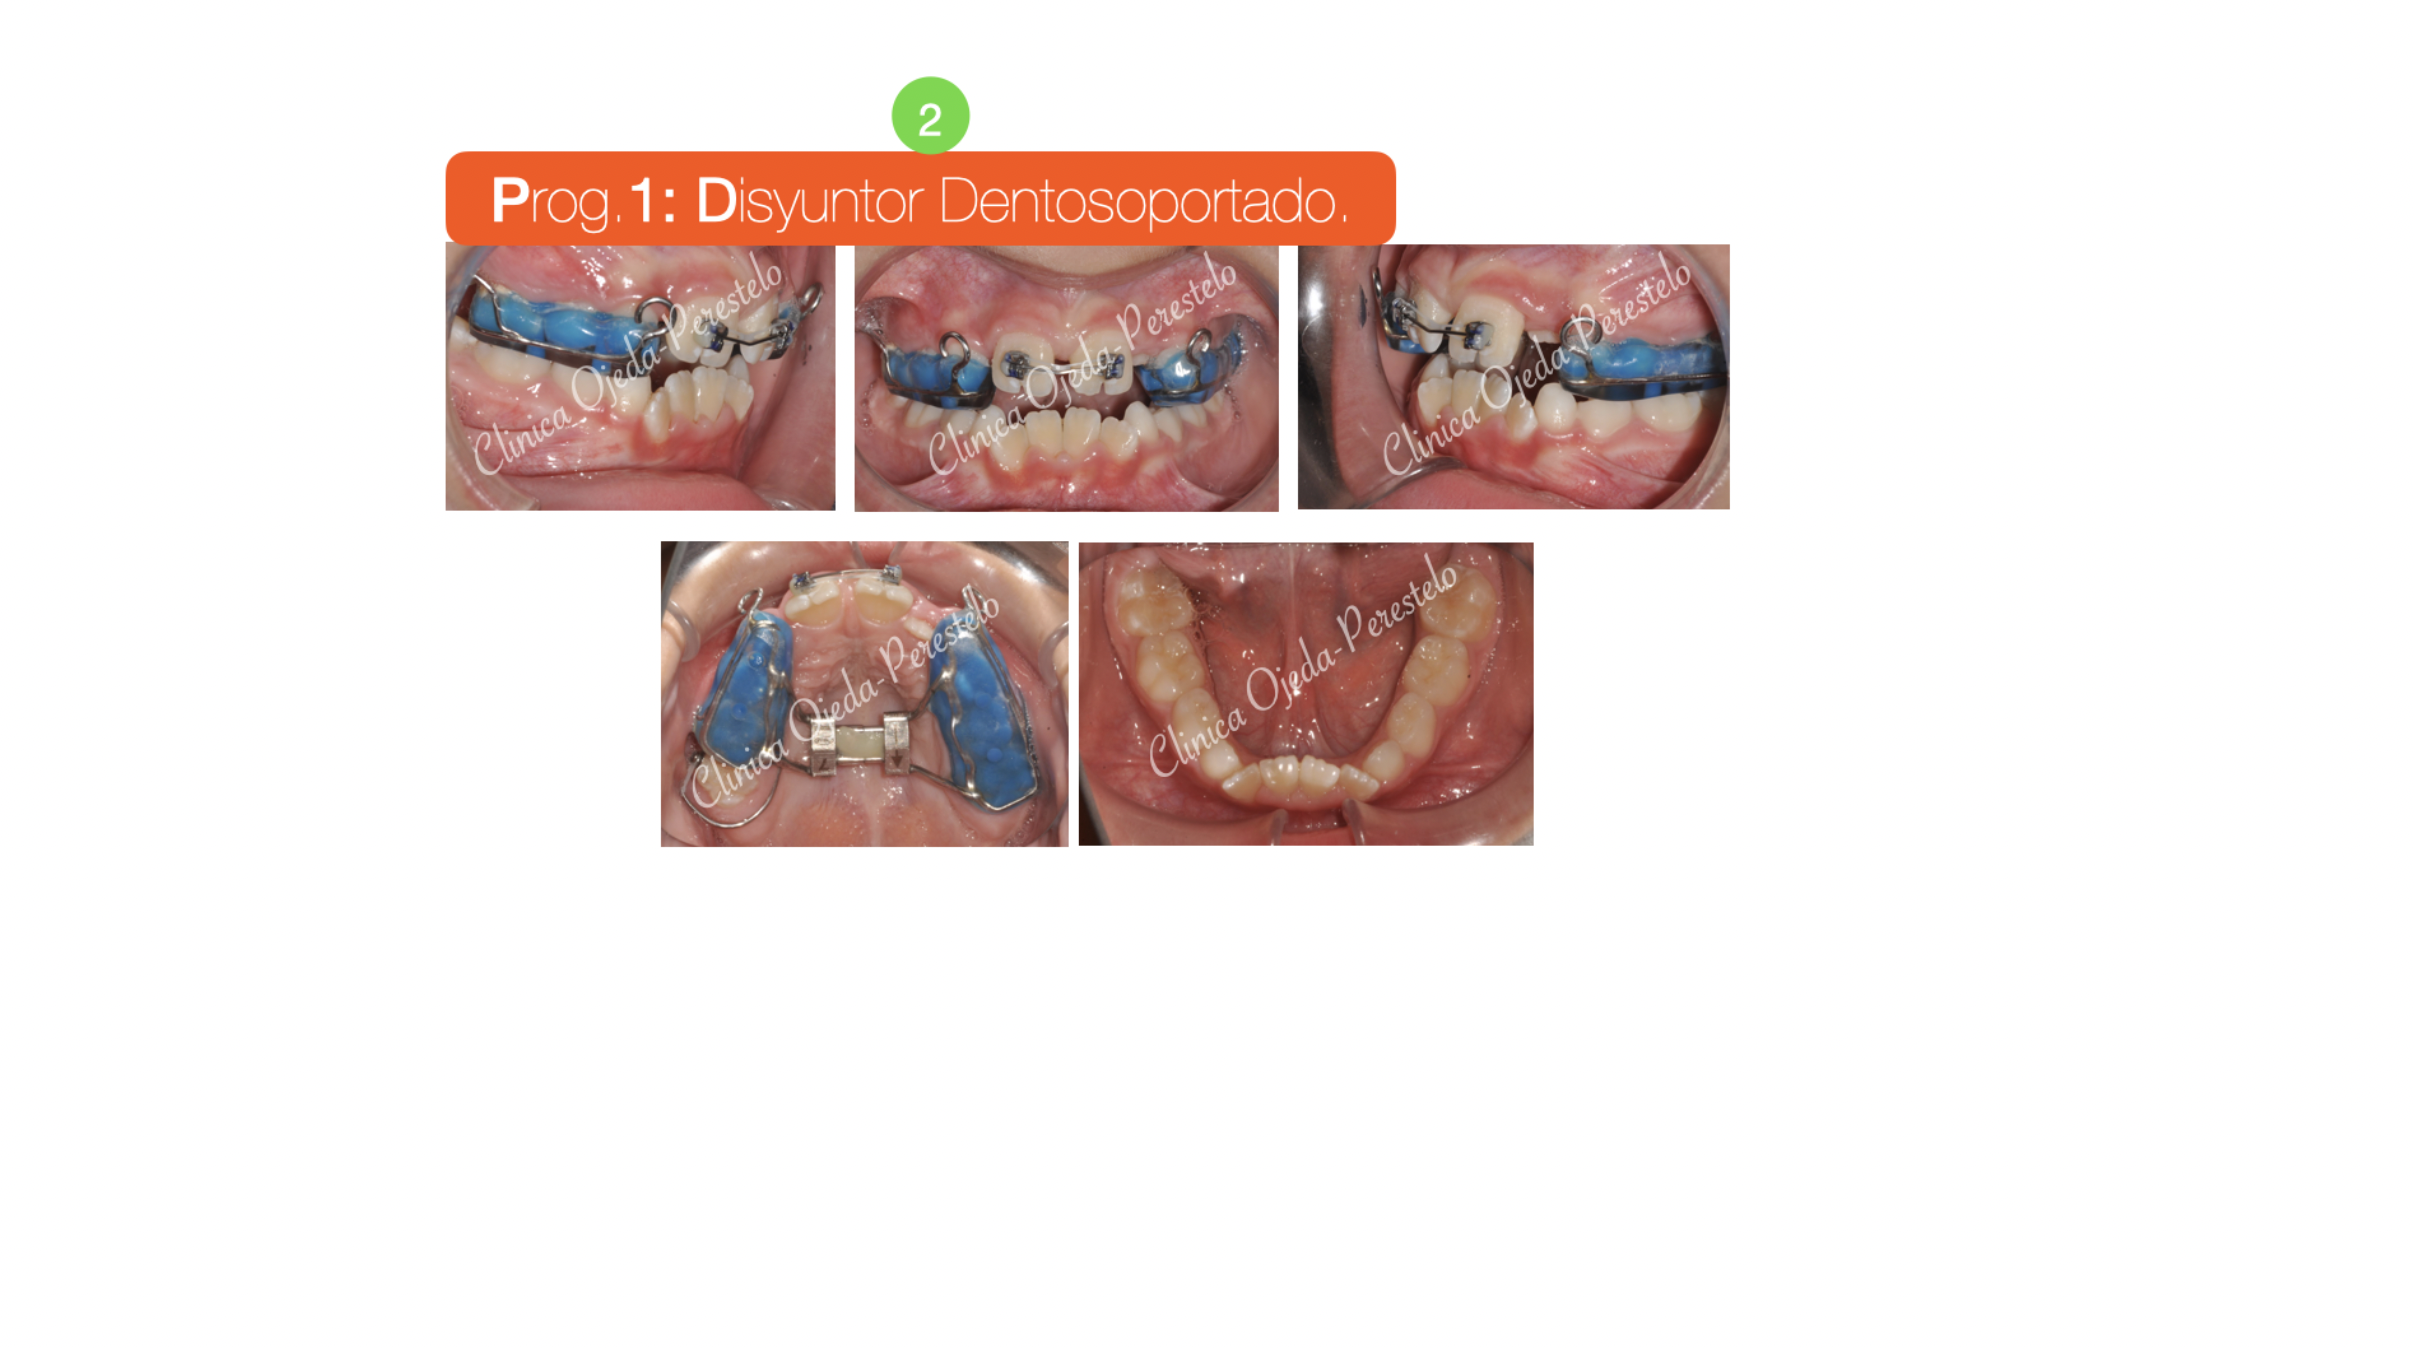

Presentamos a este niño respirador bucal y roncador con Mordida cruzada Bilateral. Decidimos colocarle un Disyuntor Dentosoportado con ganchos para Máscara Facial. Una vez terminada la fase Ortopédica (4 Meses ),comenzamos con la alineación y nivelación de los 4 incisivos con brackets superiores e inferiores (2x4 ). Quisiéramos destacar la mejoría del paciente en la función respiratoria, deglutoria y masticatoria. Sus ronquidos han desaparecido y se ha conseguido una gran amplitud en la sonrisa.